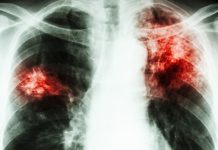

TUBERCULOZA UCIDE PE TACUTE!

Tuberculoza, sau TBC (abreviere pentru „bacilul de tubercul”) este o boală infecțioasă frecventă și, de obicei, curabilă, provocată de diferite tipuri de micobacterii, de...